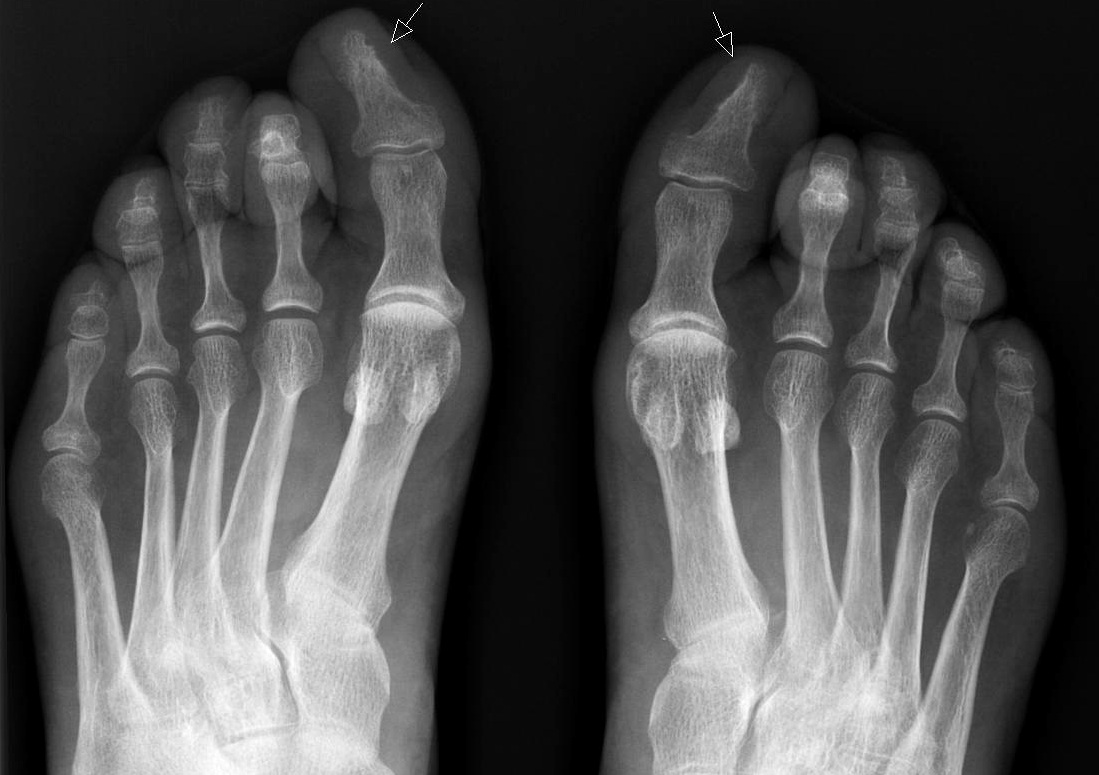

При развитии осложнений выполняется рентгенография костей стопы, чтобы исключить распространение гнойного процесса на кость.